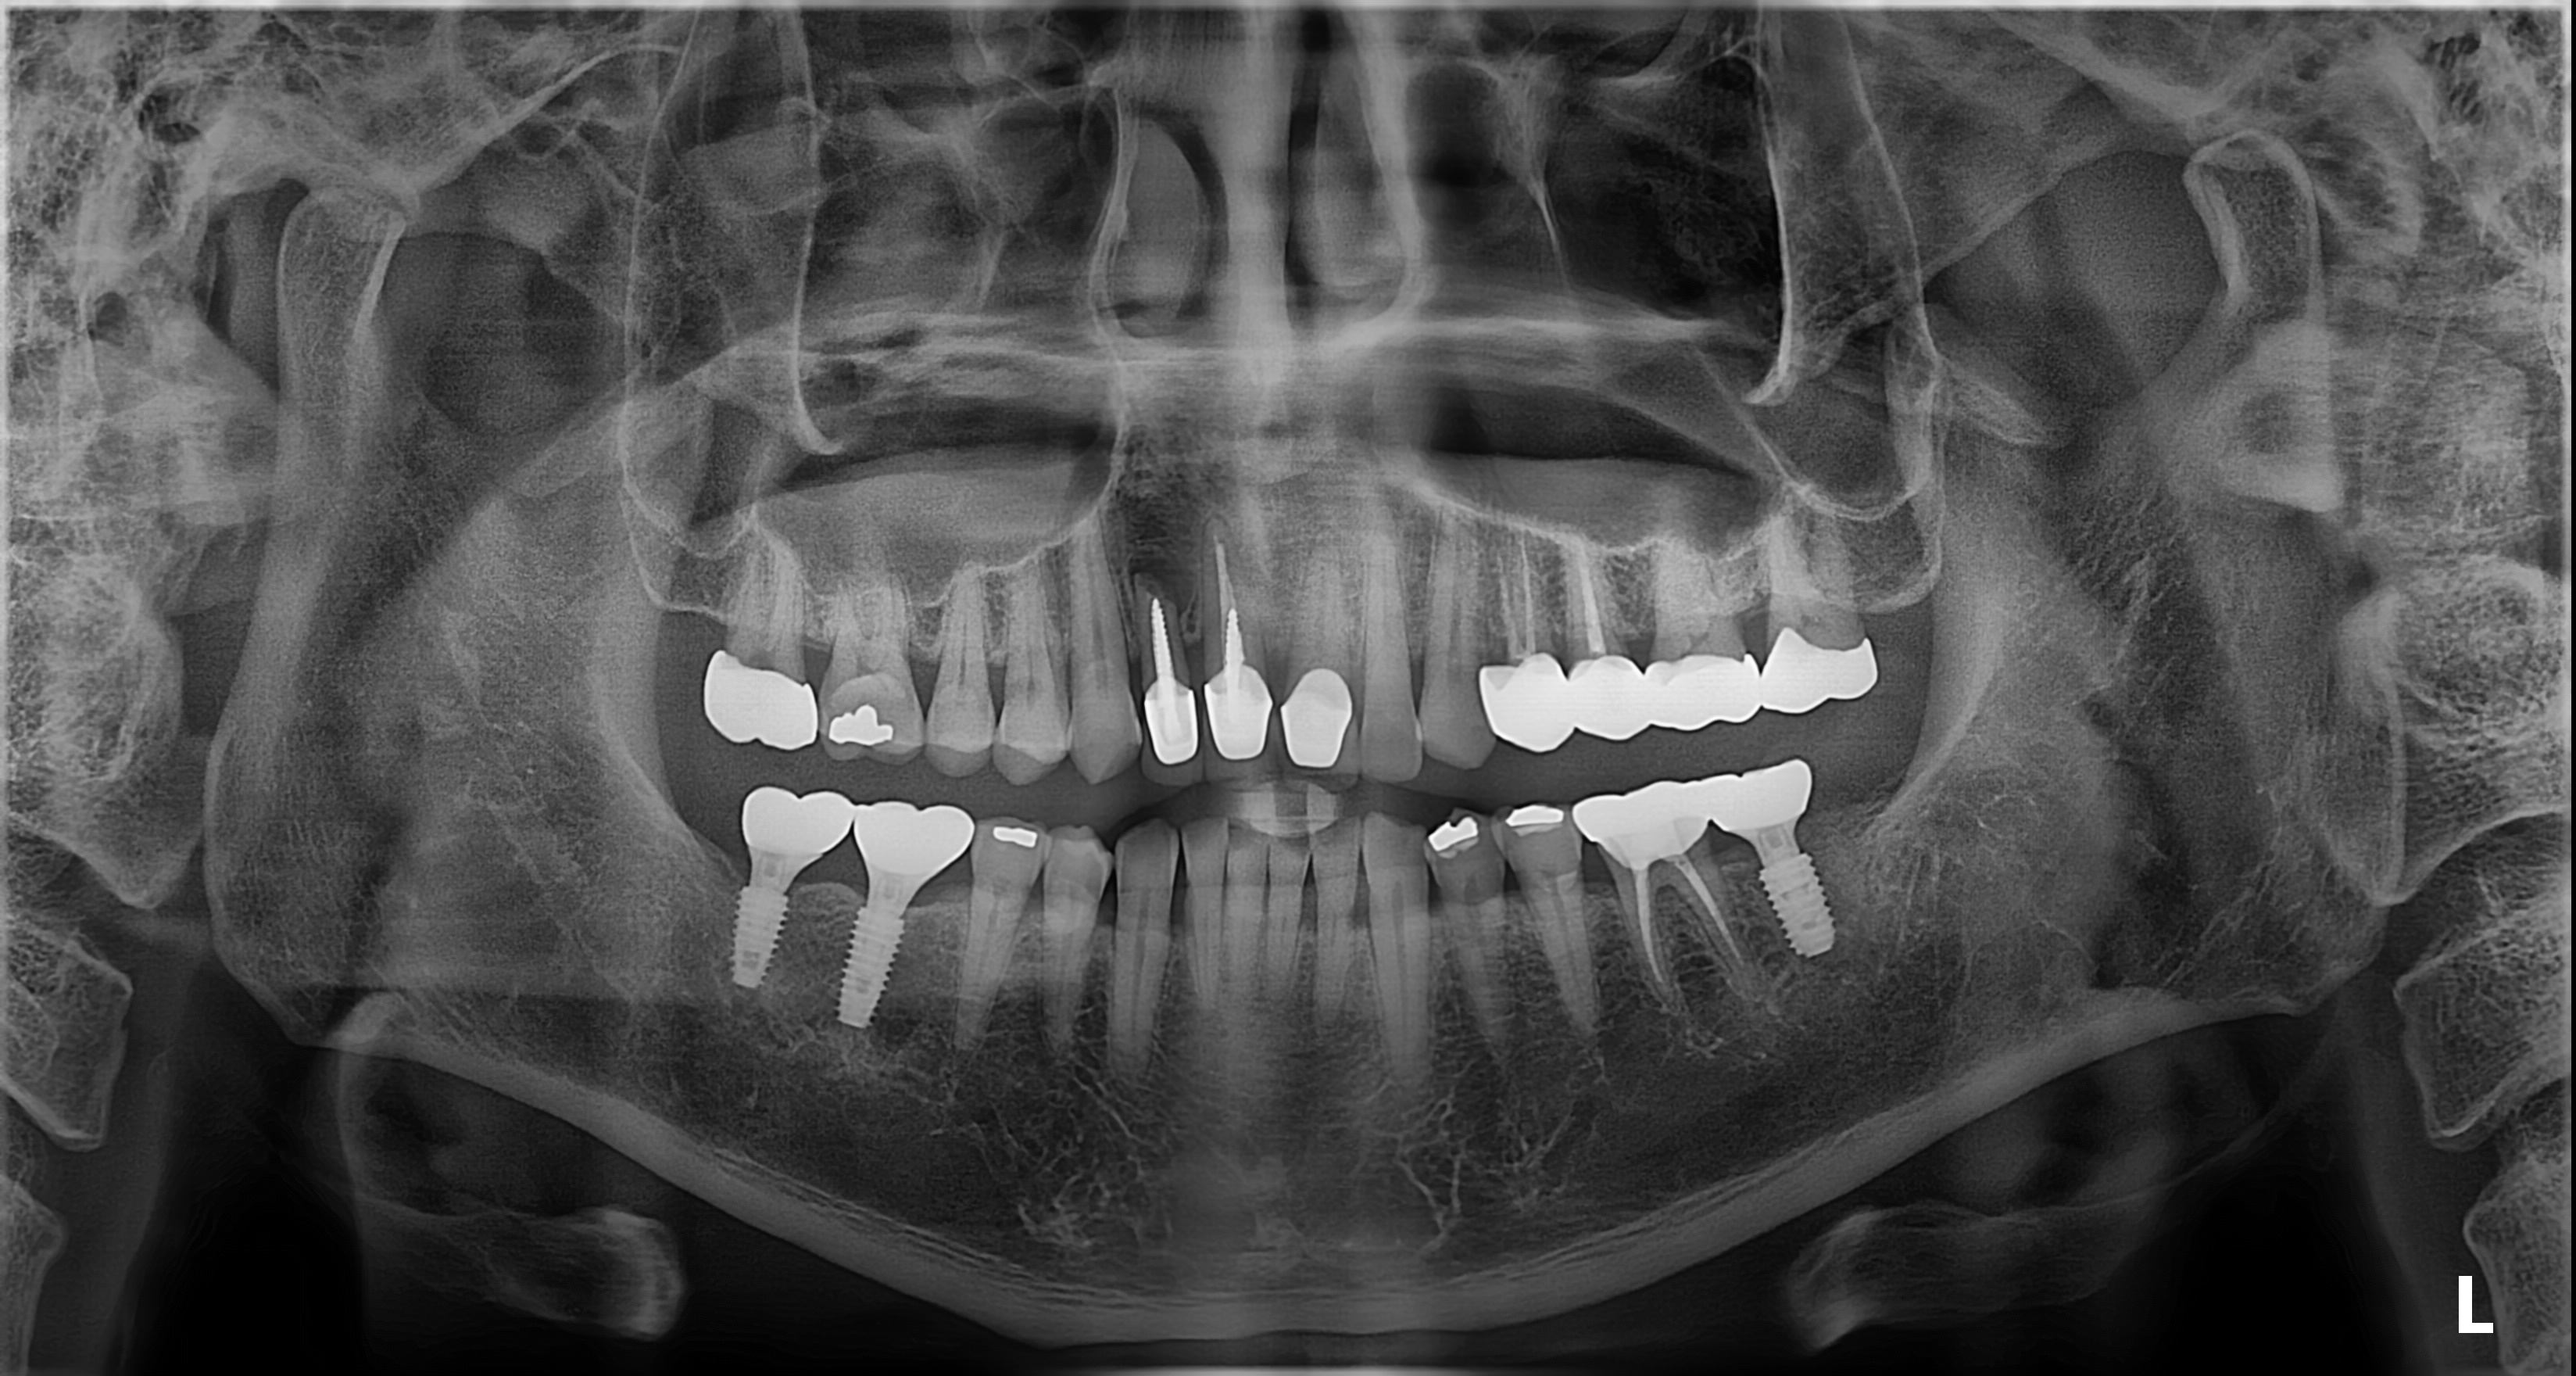

임플란트 시술 사진

임플란트의 5년 성공율은

최근 발표된 논문들까지 종합해도

90~95% 이상으로 발표되고 있습니다.

매우 높은 성공율입니다.

하지만, 실패한 임플란트를 같은 자리에

재식립했을 때의 성공률은 70%대로 떨어집니다.

(J Oral Maxillofac Surg 78:375-385, 2020)

초기에 발견하고 재식립했을 때는 성공율이 높아집니다.